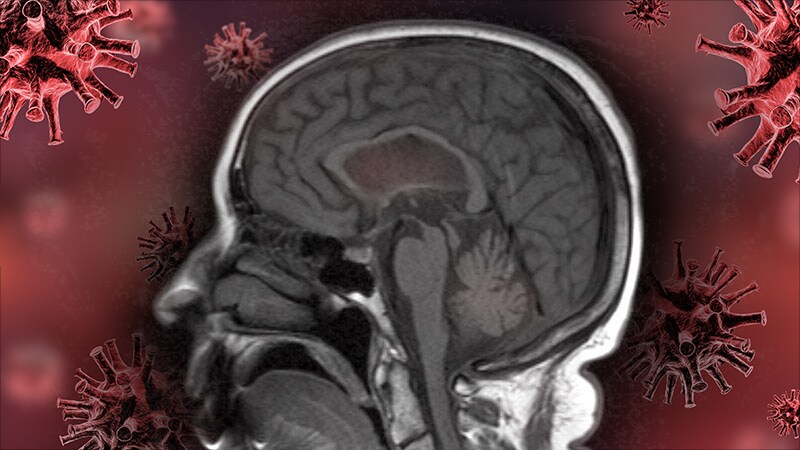

COVID-19 Linked to Increased Risk for Parkinson's -